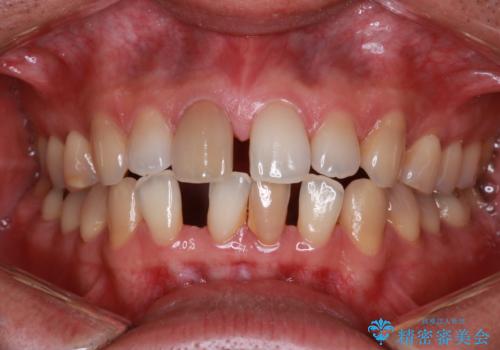

- 笑ったときに八重歯が見えることを主訴に来院されました。

下の前歯が一本足りない患者様でしたので、シミュレーションを作り、事前に患者様と治療ゴールのイメージをしっかり共有したうえでインビザラインを用いて治療を行っています。

下顎の前歯が一本ない場合は上下の正中は合いません。